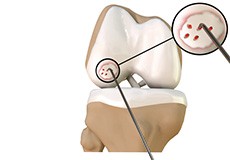

Articular Cartilage and Menisci of the Knee

Movement of the bones causes friction between the articulating surfaces. To reduce this friction, all articulating surfaces involved in the movement are covered with a white, shiny, slippery layer called articular cartilage. The articulating surface of the femoral condyles, tibial plateaus and the back of the patella are covered with this cartilage. The cartilage provides a smooth surface that facilitates easy movement.

To further reduce friction between the articulating surfaces of the bones, the knee joint is lined by a synovial membrane that produces a thick clear fluid called synovial fluid. This fluid lubricates and nourishes the cartilage and bones inside the joint capsule.

Within the knee joint, between the femur and tibia, are two C-shaped cartilaginous structures called menisci. Menisci function to provide stability to the knee by spreading the weight of the upper body across the whole surface of the tibial plateau. The menisci help in load-bearing i.e. it prevents the weight from concentrating onto a small area, which could damage the articular cartilage. The menisci also act as a cushion between the femur and tibia by absorbing the shock produced by activities such as walking, running and jumping.